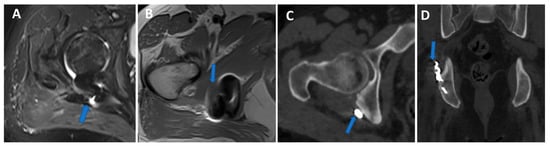

Figure 6.

Traumatic anterior shoulder dislocation with rotator cuff complete tear and Hill Sachs lesion. On the 2D 1 mm axial and coronal reconstructed VNCa images (A,B), a subtle depression of the posterior aspect of the humeral head is visible, with mild edema coded in green on the superimposed map (arrow). The 3D VNCa image (C) clearly shows the passage of contrast material in the sub-acromial space (arrow). On the coronal 1 mm reconstructed iodine map image (D), the complete rupture of the rotator cuff is beautifully confirmed (arrow). On the sagittal LNC images (E,F), it is possible to identify (arrow on (F)) and quantify (ROI on (E)) the presence of atrophy of the muscle belly.